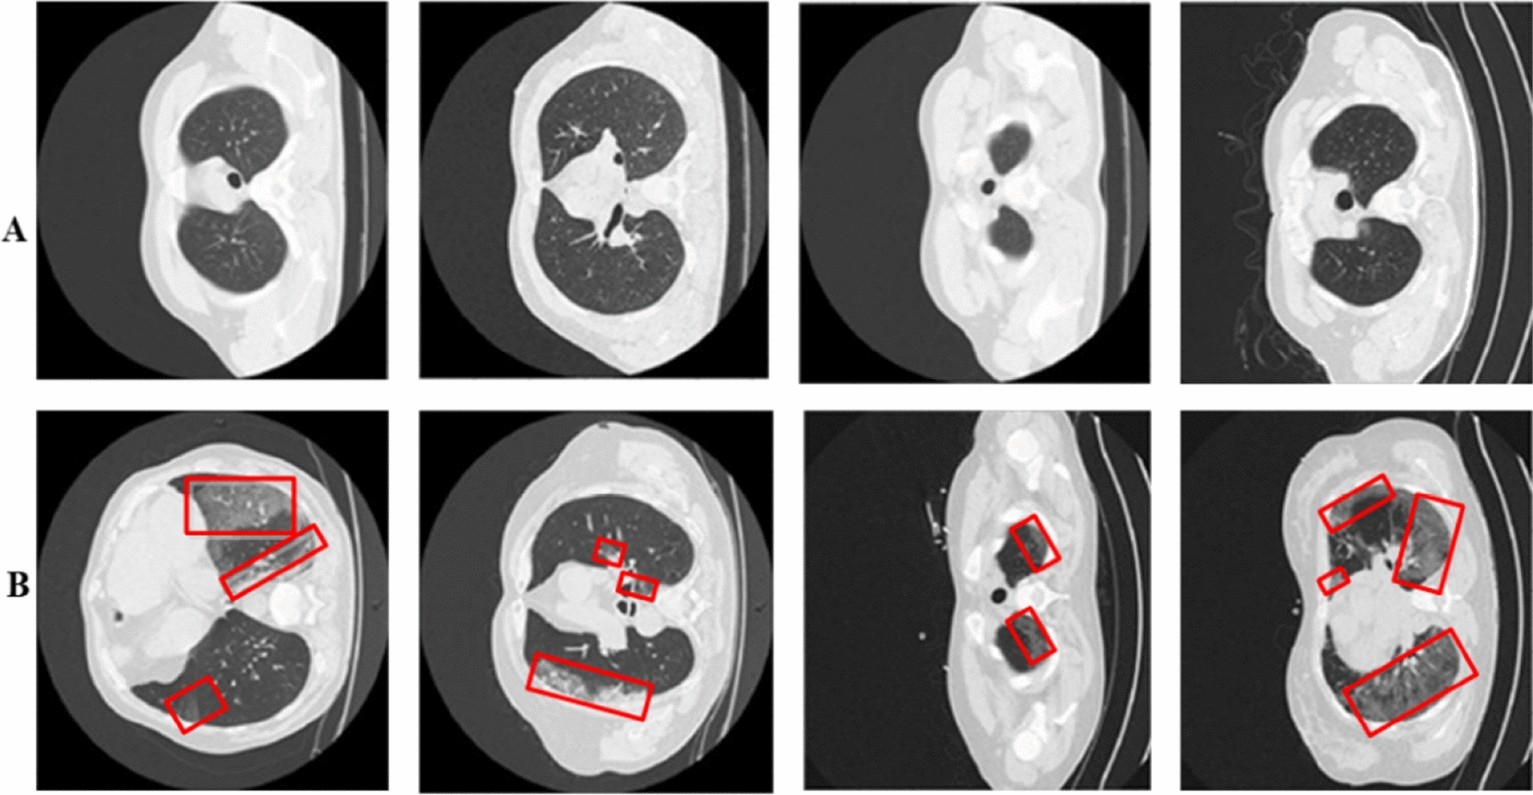

Figure 5

Panels (A,B) represent COVID-19 infected vs. Healthy samples. While the infected regions are red highlighted.